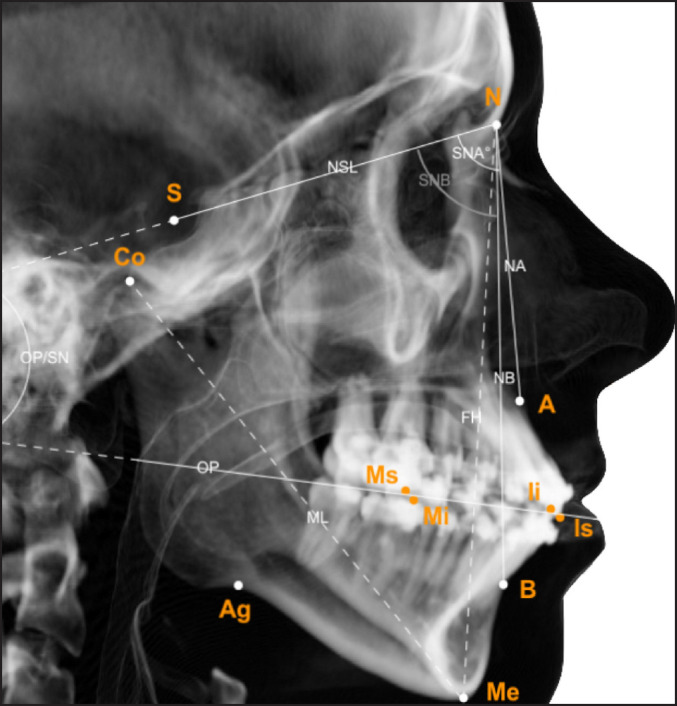

Material and methods: Nineteen patients with juvenile idiopathic arthritis of the temporomandibular joint (TMJ) and dentofacial deformities were included. All patients were treated with combinations of bilateral sagittal split osteotomy, Le Fort I and/or genioplasty, between September 10, 2007 and October 17, 2017. Analysis of patient symptoms and clinical registrations, and frontal/lateral cephalograms was performed pre- and postoperative and long-term (mean: 3.8 and 2.6 years, respectively).

Results: Patients experienced no changes in orofacial symptoms or TMJ function, and stable normalisation of horizontal and vertical incisal relations at long-term (horizontal overbite; vertical overbite: P < 0.05). Mandibular lengthening was achieved postoperatively (from mean 79.7 to 87.2 mm; P = 0.004) and was stable. Sella-nasion to A point (SNA) and sella-nasion to B point (SNB) angles increased postoperatively (SNA, mean 79.9° to 82.8°; P = 0.022 and SNB, mean 73.9° to 77.8°; P = 0.003), however, largely reverted to preoperative status at long-term.